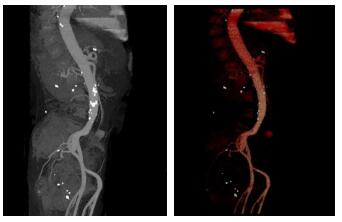

腹部CT平扫示, 十二指肠水平部增厚, 中下腹肠系膜增厚, 肠系膜静脉增粗。进一步行全腹部增强CT示, 肠系膜上动脉远端分支假性动脉瘤形成, 腹盆腔积血、积液, 肠系膜渗出。左侧髂动脉分叉处瘤样扩张。十二指肠水平部水肿增厚。双肾结石。急诊拟“肠系膜上动脉假性动脉瘤破裂出血”收住入院。入院诊断:肠系膜上动脉假性动脉瘤破裂出血、腰椎感染、心脏瓣膜置换术后、冠状动脉粥样硬化、心肌桥、高血压。

| 图 2 患者全腹部增强CT结果(示肠系膜上动脉远端分支假性动脉瘤形成, 腹盆腔积血、积液, 肠系膜渗出) |